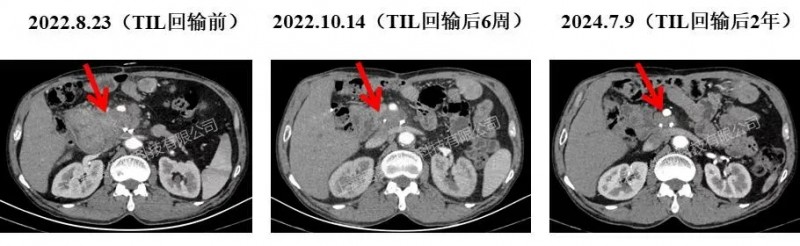

案例2(晚期胰腺癌):复发病灶大幅缩小,39个月恢复正常生活

另一例晚期胰腺癌患者,在手术切除胰腺肿瘤后,复查时确诊肿瘤复发并伴随肝内转移,随后入组接受GC101 TIL疗法治疗。

结果显示:单次回输TIL细胞6周后,患者胰头部位的10cm复发病灶快速缩小至3cm,残余肝转移病灶完全消失,多个肿瘤标记物也恢复至正常水平;此后历次复查显示,病灶持续缩小至1cm左右,超声提示为钙化斑(已无代谢活性)——截至目前,患者已恢复正常生活超过39个月!

▲图源“JUNCELL”,版权归原作者所有,如无意中侵犯了知识产权,请联系我们删除